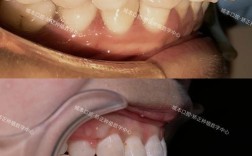

传统金属托槽矫正是应用最广泛的方法,通过将金属托槽用黏合剂固定在牙齿表面,再利用弓丝与托槽的连接,施加持续轻力引导牙齿移动,该方法矫治力稳定,适用范围广,无论是简单拥挤还是复杂错颌畸形均能有效解决,但缺点是美观性较差,托槽易刮伤口腔黏膜,且口腔清洁难度较大,需特别注意避免食用过硬、黏性食物。

自锁托槽矫正是在传统托槽基础上升级的技术,托槽自带闭锁装置,无需结扎丝或橡皮圈固定弓丝,减少了弓丝与托槽的摩擦力,这一优势使得牙齿移动更高效,可缩短矫治疗程(通常比传统方法缩短3-6个月),同时复诊间隔可适当延长,患者不适感也相对较轻,其费用较传统托槽高20%-30%,且对医生操作技术要求更高。